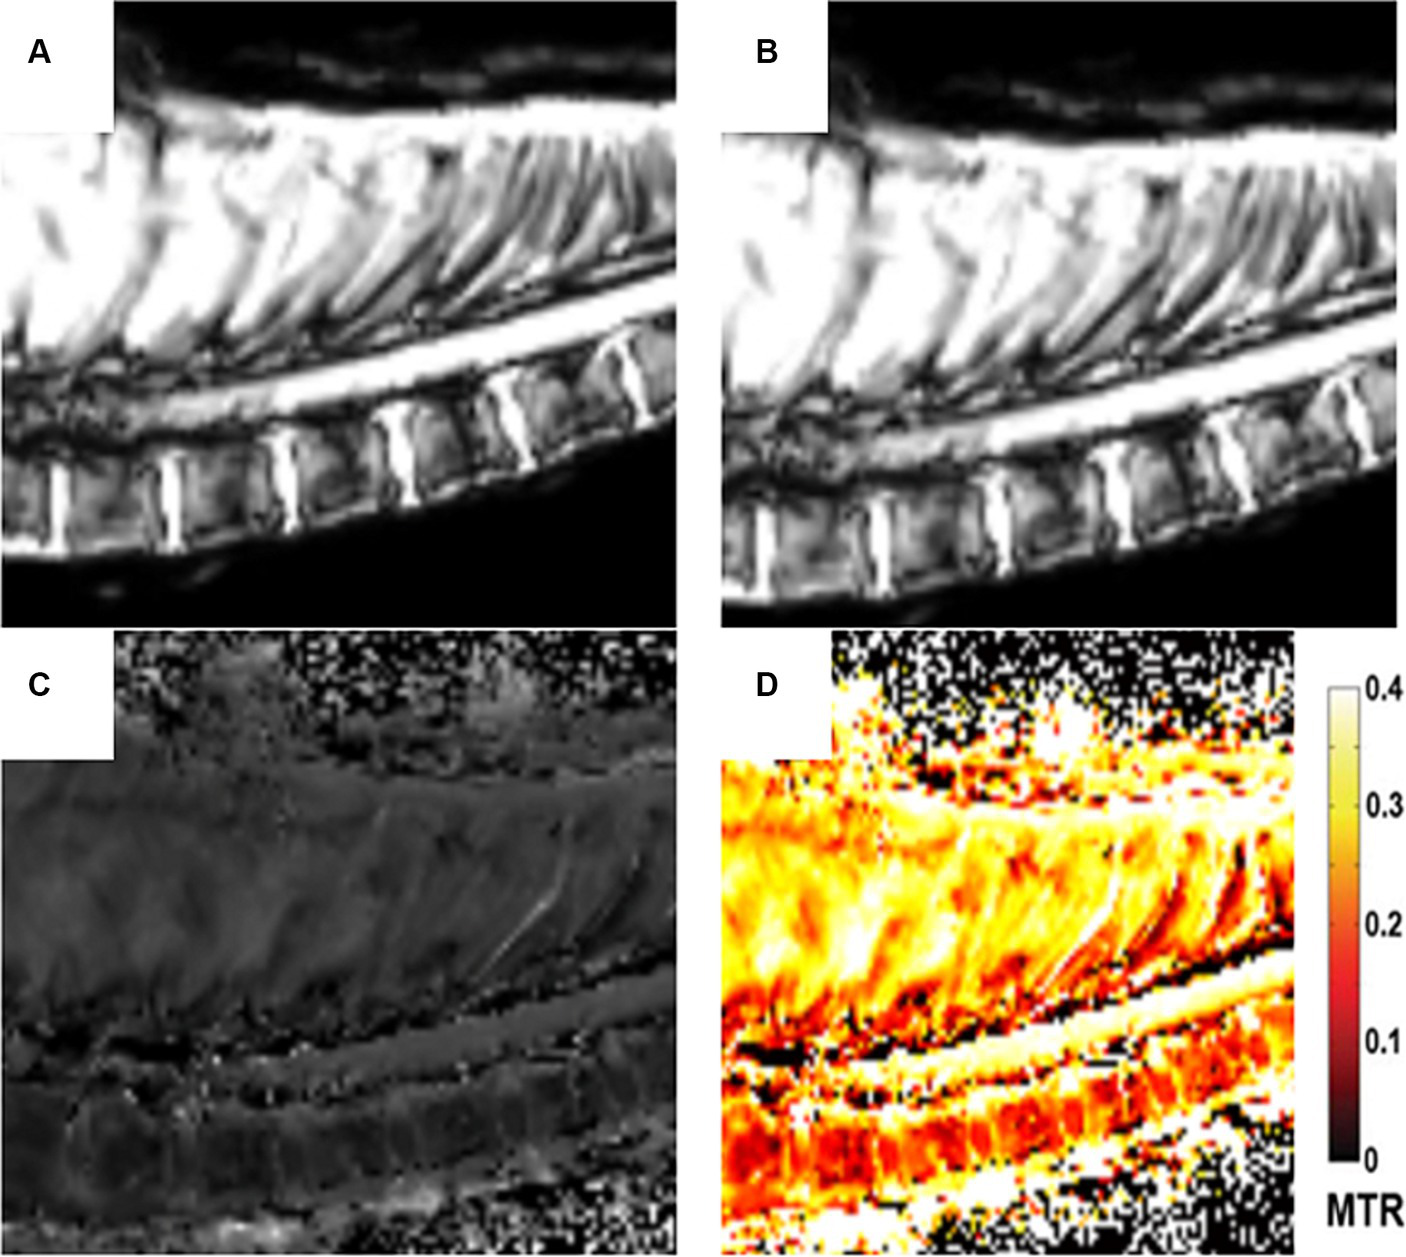

Four types of images were obtained from the magnetization transfer sequences: image without the off-resonance RF with the signal M0, image with the off-resonance saturation RF with the signal MSAT, image calculated with the MTR pixel-by-pixel algorithm (MTR = (M0-MSAT)/M0) and image of the MTR color map. These images are displayed in Figure 1.

Figure 1. Different sets of images of the MTR sequence: Image without the off-resonance RF with the signal M0 (A). Image with the off-resonance saturation RF with the signal MSAT (B), Image calculated with the MTR pixel-by-pixel algorithm (MTR = (M0-MSAT)/M0) (C). Image of the MTR color map (D).